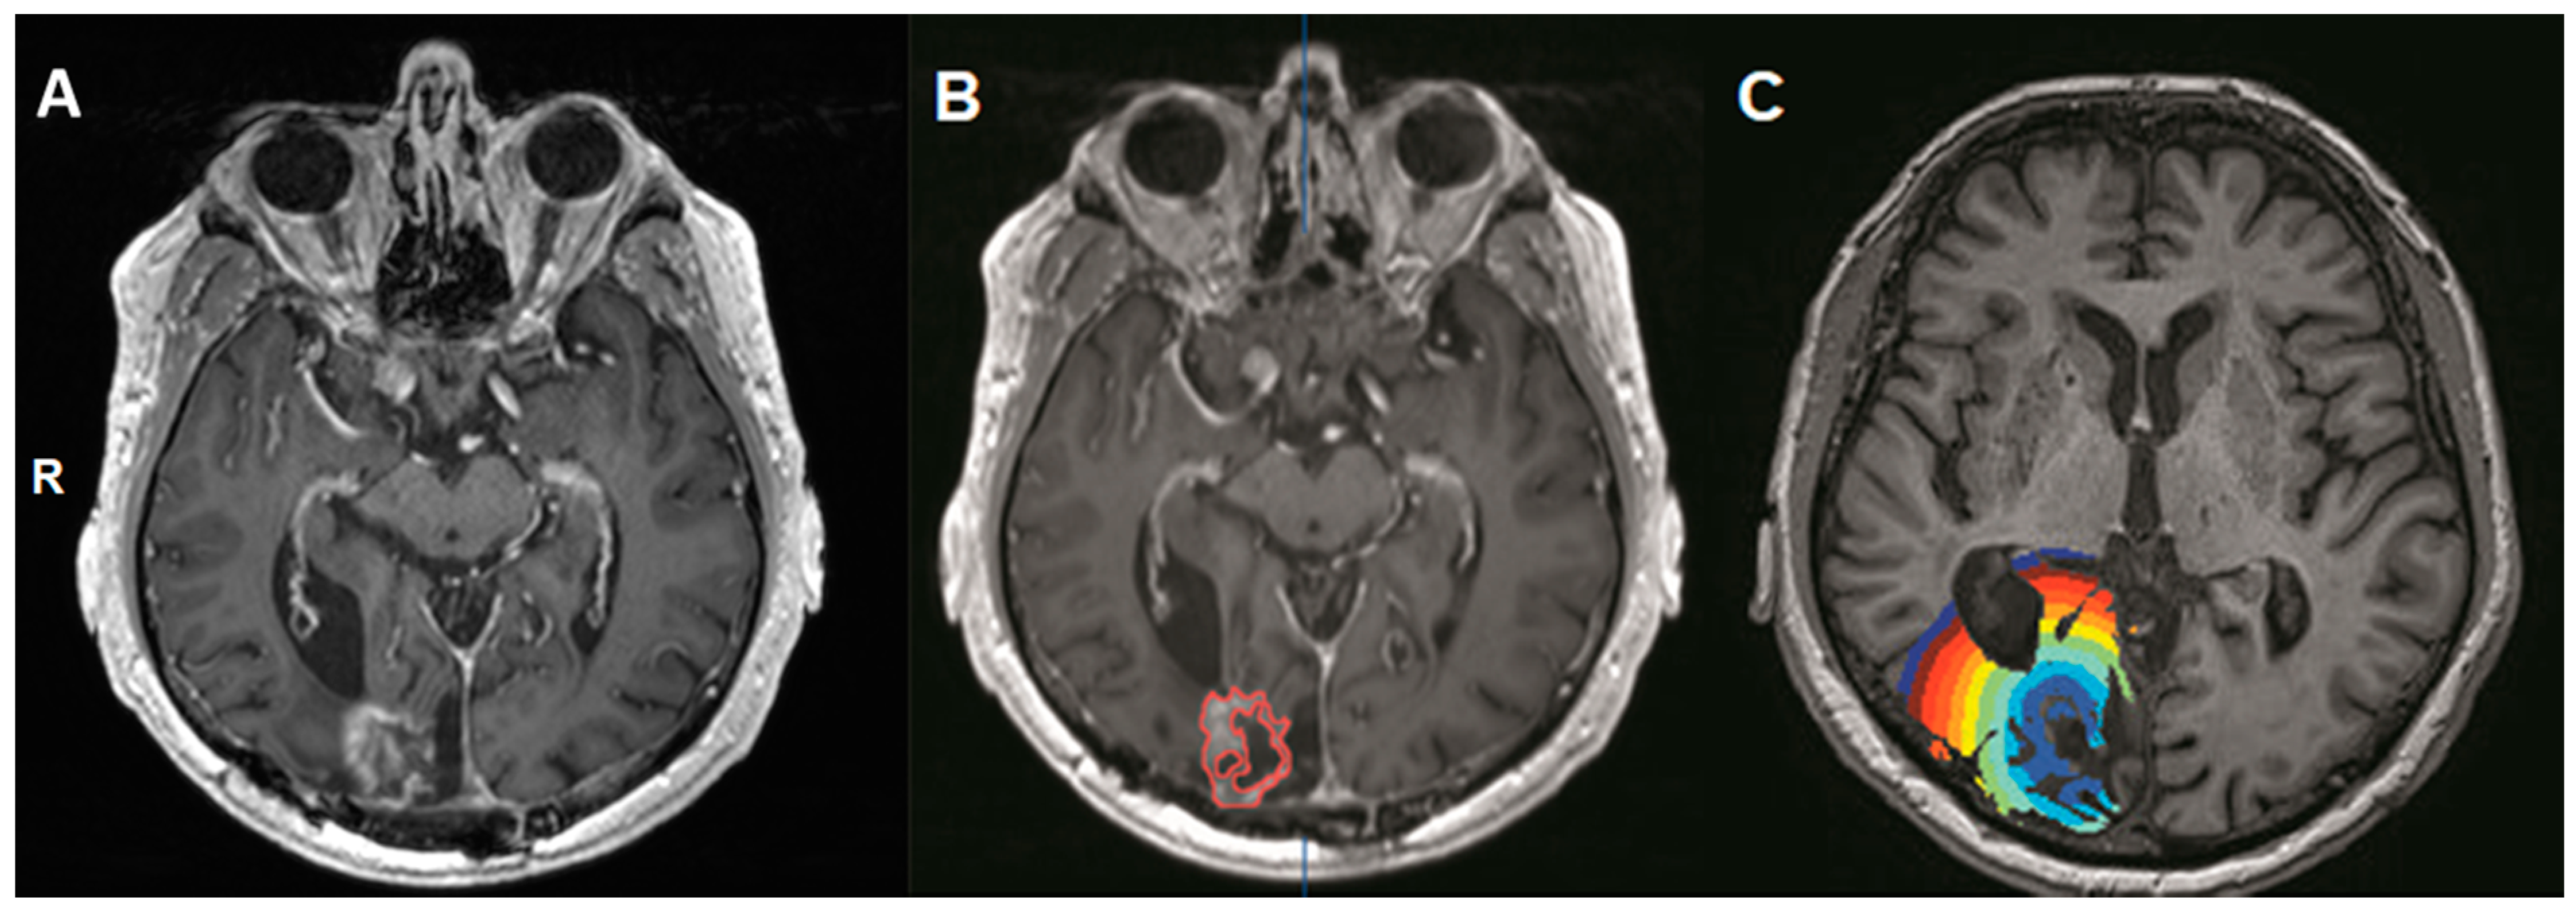

2.3. Masking of the Contrast-Enhancing Lesion (Volume-Of-Interest, VOI)

BOLD-CVR Findings for Patients with Radiation Necrosis and Newly Diagnosed Glioblastoma